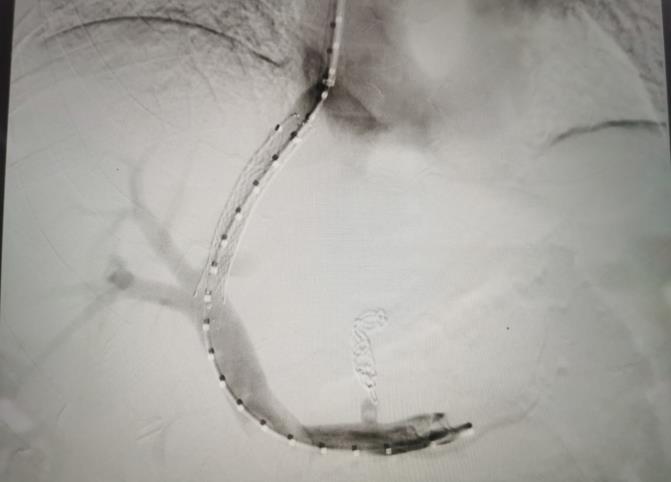

經(jīng)過我院血管介入科醫(yī)療團(tuán)隊的精心準(zhǔn)備,患者在數(shù)字減影血管造影機(jī)(DSA)導(dǎo)引下,順利經(jīng)頸靜脈入路進(jìn)入下腔靜脈并成功穿刺了門靜脈右支主干,術(shù)中栓塞了曲張的胃冠狀靜脈-食管靜脈叢將支架植入肝實(shí)質(zhì)內(nèi),支架兩端分別置于門靜脈和肝靜脈內(nèi),術(shù)程歷時2小時,術(shù)中患者時刻保持清醒,手術(shù)切口僅5毫米,術(shù)后第2天恢復(fù)飲食,腹脹、腹水癥狀明顯好轉(zhuǎn),未出現(xiàn)嘔血、黑便及肝性腦病等并發(fā)癥,術(shù)后第3天康復(fù)出院。